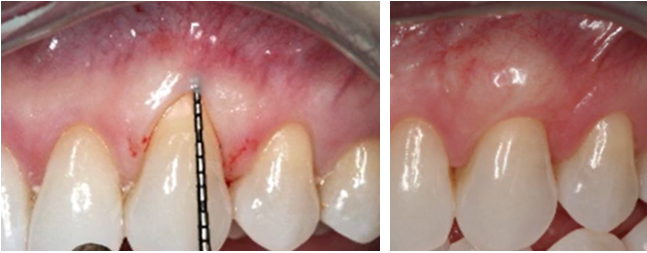

There is a simple way to check the thickness of the attached gingiva using a regular probe.

Checking the gingival biotype (thickness of attached gingiva): on the left, the probe is translucent and clearly visible through the gingiva – a sign of a thin biotype; on the right, the probe is poorly visible – a sign of a thick biotype. YouTube/ Implantarium/ Rauf Aliyev

If the tip of the probe is clearly visible through the gingiva, it is closer to the thin phenotype; if it is almost invisible, then it is thick.

But in reality, extreme cases are almost never encountered, as this clinical case confirms. Furthermore, it is possible to increase the thickness of attached gingiva, that is, change the phenotype, through soft tissue grafting. Therefore, the term “biotype” has been abandoned in favor of “phenotype,” because “biotype” implies something fundamentally inherent in nature and cannot be changed.

An example of increasing the thickness of attached gingiva using soft tissue plastic surgery. YouTube/ Implantarium/ Rauf Aliyev